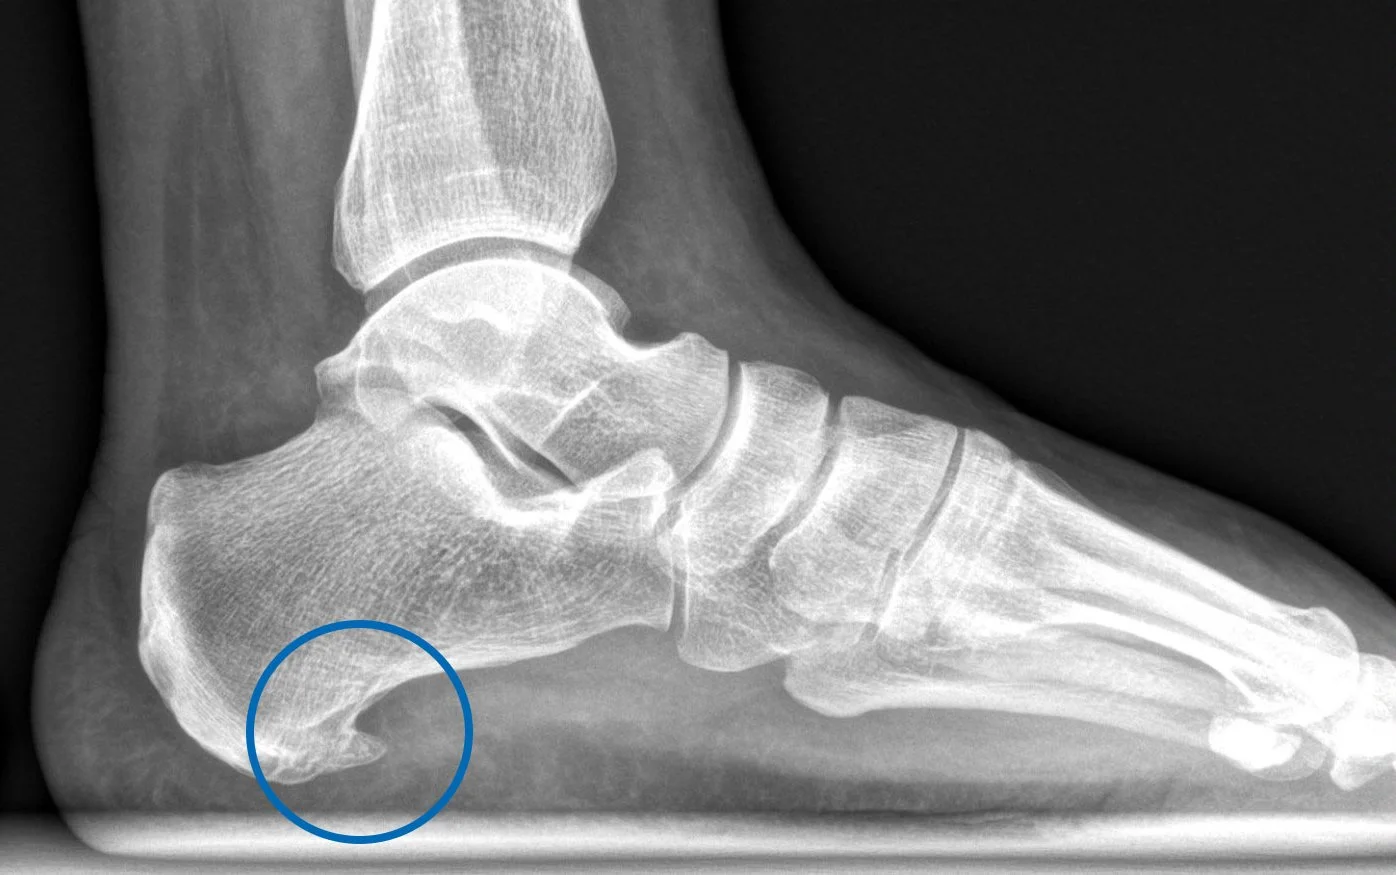

Luxación de tobillo: Todo lo que debes saber para recuperarte y volver al deporte con seguridad en 2026

Si sufriste una luxación de tobillo o un esguince, este artículo te ayudará a entender tu lesión, conocer los tratamientos más efectivos y aprender los mejores ejercicios para recuperar tu movilidad y volver a tu vida activa sin miedo.